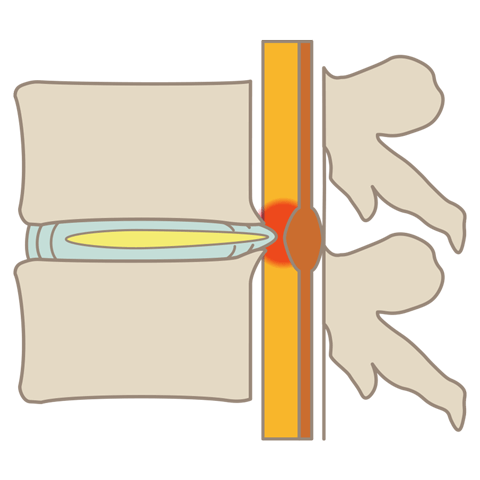

腰部脊柱管狭窄症

腰部脊柱管狭窄症とは、背骨にある神経の通り道「脊柱管」が狭くなる疾患です。腰痛や足の神経障害、歩行困難などの症状を引き起こします。

坐骨神経痛

坐骨神経痛とは、腰椎椎間板ヘルニアや腰部脊柱管狭窄症などを原因とし、腰から下部の臀部や脚部に痛みや痺れを感じる症状です。